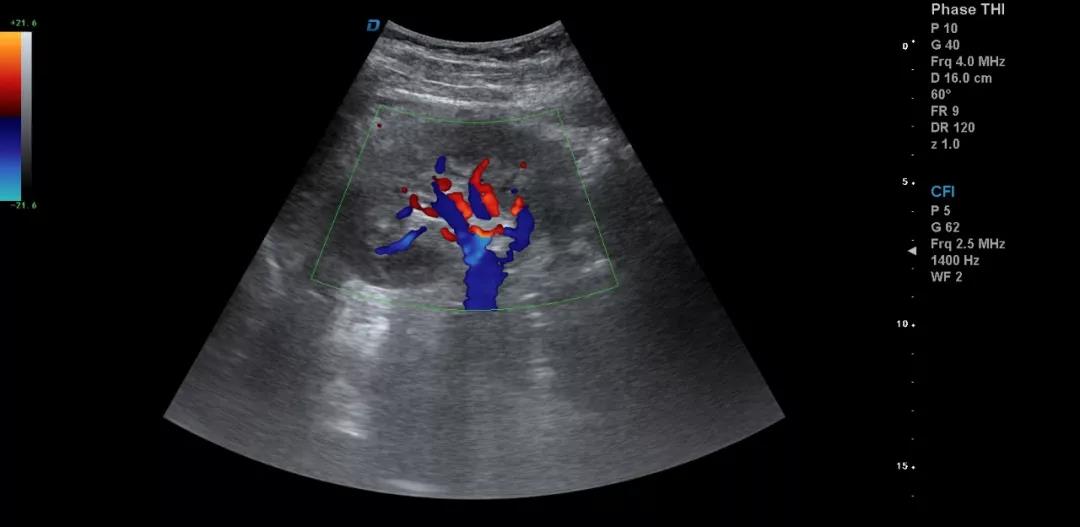

3.注意在工作中積累超聲資料

典型圖片、經典病例圖片、動態影像資料積累的多了分析總結之后就提高了。疑難病例資料積累后,可以隨訪病人,然后總結得到的臨床資料和病理結果。

有了手術結果和病理才會有真正的提高。按器官、按系統、按學科進行總結每一個、每一類疾病正常及異常圖片就是知識的積累。